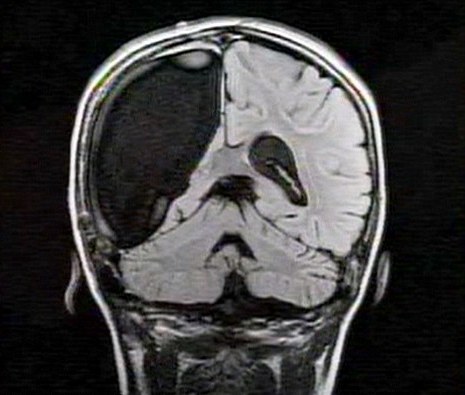

卡梅倫莫特在3歲那年患上一種被稱作大腦功能紊亂“拉斯穆森”綜合癥,這種病癥誘發(fā)患者的無序暴力行為和嚴(yán)重的癲癇。醫(yī)生建議,治療這種病癥只能通過嘗試消除引發(fā)此癥狀的大腦組織。而手術(shù)讓莫特失去了幾乎整個(gè)半邊的大腦。

據(jù)悉,莫特在手術(shù)后已經(jīng)可以跑動(dòng)和玩耍,她在術(shù)后的第四周離開了醫(yī)院。醫(yī)生表示,雖然右半邊大腦的切除可能會(huì)給莫特帶來半身不遂的風(fēng)險(xiǎn),但孩子剩余的大腦仍具有很強(qiáng)的重組和布線能力。